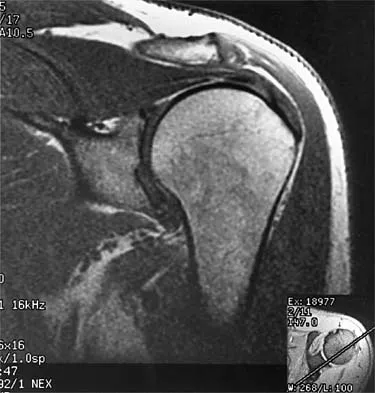

A 47-year-old male tennis player has pain in his nondominant shoulder that has failed to respond to 4 months of nonsurgical management. Examination reveals acromial tenderness and pain at the supraspinatus tendon insertion. He has a positive impingement sign, pain on forward elevation, and minimal cuff weakness. The MRI scans are shown in Figures 30a and 30b. To completely resolve his symptoms, treatment should consist of

The MRI scans show a mesoacromion with tendonopathy of the supraspinatus. The history and physical findings indicate that the patient has a symptomatic os acromiale. Simple excision of the unstable os acromiale has not yielded consistently good results. Meticulous internal fixation using tension banding with cannulated screws and autologous bone grafting has shown good results for this problem. Hutchinson MR, Veenstra MA: Arthroscopic decompression of shoulder impingement secondary to os acromiale. Arthroscopy 1993;9:28-32.